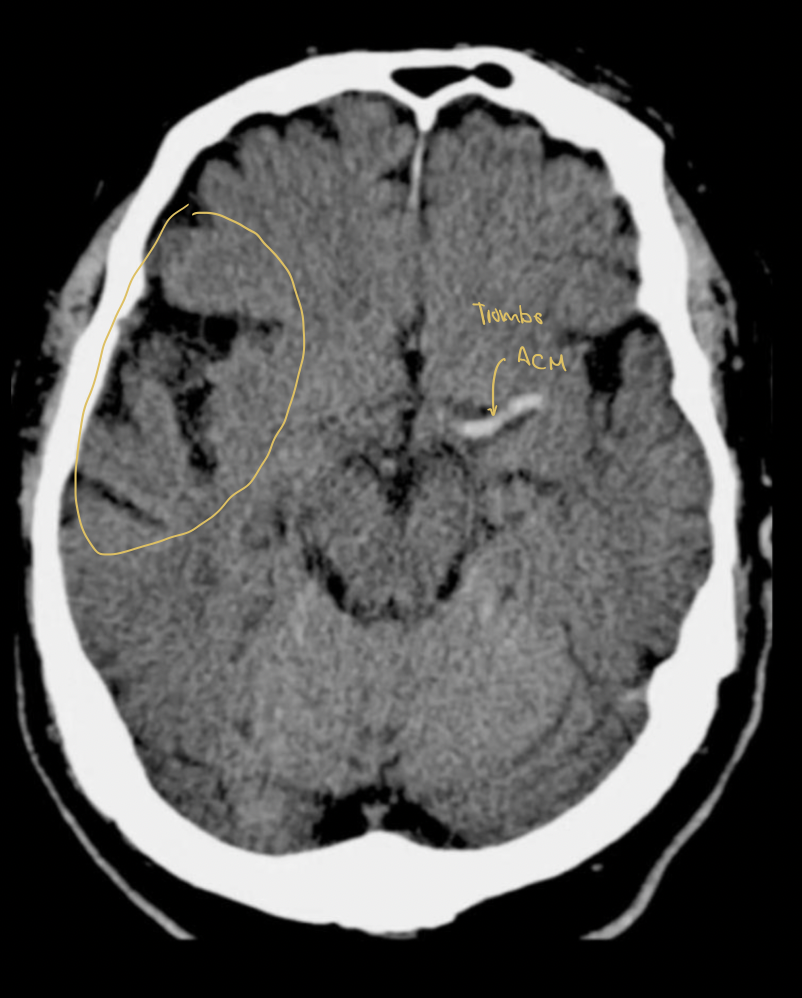

18

Q

Diagnóstico:

A

EVC isquémico en fase a subaguda (24 a 72 h)